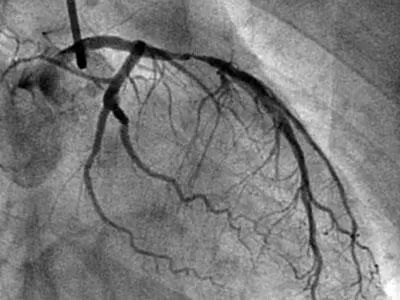

冠脉造影是直接透视下,通过不同角度观察心脏血管的情况,医生更直观地从不同角度来看心脏的各个血管的狭窄情况和程度,相对来说比较准确。

冠脉造影,是需要把导管通过手腕或大腿根的血管,送入到心脏的血管开口,随后再把造影剂通过导管推入心脏血管,造影剂进入心脏血管的同时,立即透视,在X线下就能看到即时的心脏血管影像,也就能看到心脏血管有没有狭窄,以及狭窄的程度。